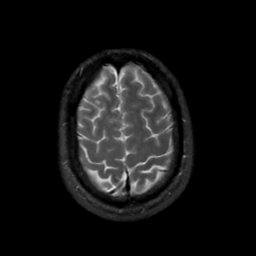

MR Study #2, February 17, 1991 -- Slice #42